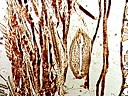

大鼠环跳穴皮下组织铺片,胆碱酯酶反应,在脂肪细胞下方有细神经纤维,箭头示脂肪细胞下方有细神经纤维